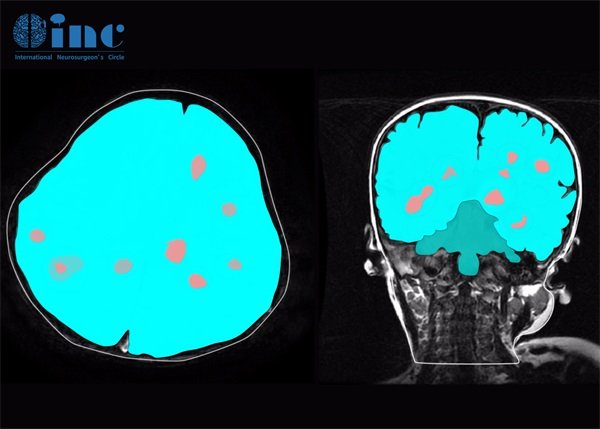

在CT扫描中,海绵状脑血管瘤的表现依赖于其血管内血液和周围组织的影响。通常情况下,海绵状脑血管瘤是由于脑内小血管的异常扩张而形成,一般呈现为相对低密度影。

CT检查时,高分辨率和对比度的图像能够帮助识别海绵状脑血管瘤的形态特征。例如,海绵状脑血管瘤在扫描中可能出现局部的“蜂窝状”影像,具有移位效应。

然CT并不是评估海绵状脑血管瘤的最佳选择,MRI扫描更加敏感,在评估病变的详细特征方面更具优势,因此CT通常被用作初期筛查。

除了CT,MRI(磁共振成像)也是一种常用的影像学工具。MRI通过高频率的磁场可以更清晰地显示脑血管结构和异常病变,因而具有更高的特异性和敏感性。